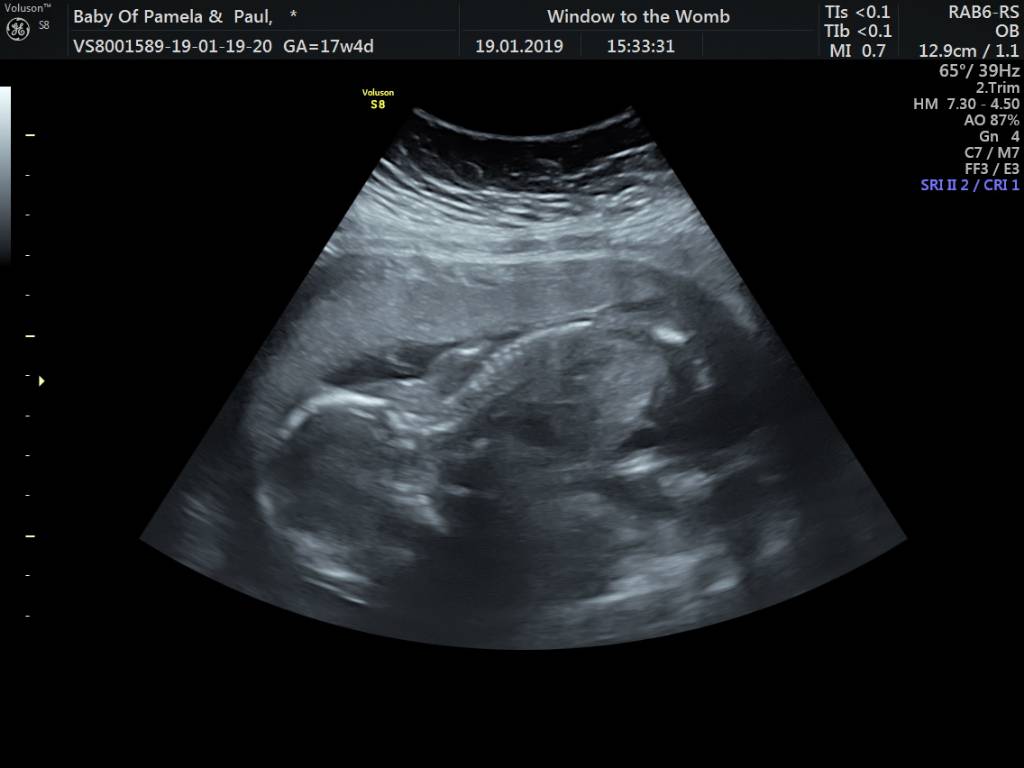

U nas 18 tydzień i też jeszcze nie wiadomo.U nas 16 tydzień póki co nie wiadomo co będzieZobacz załącznik 940258